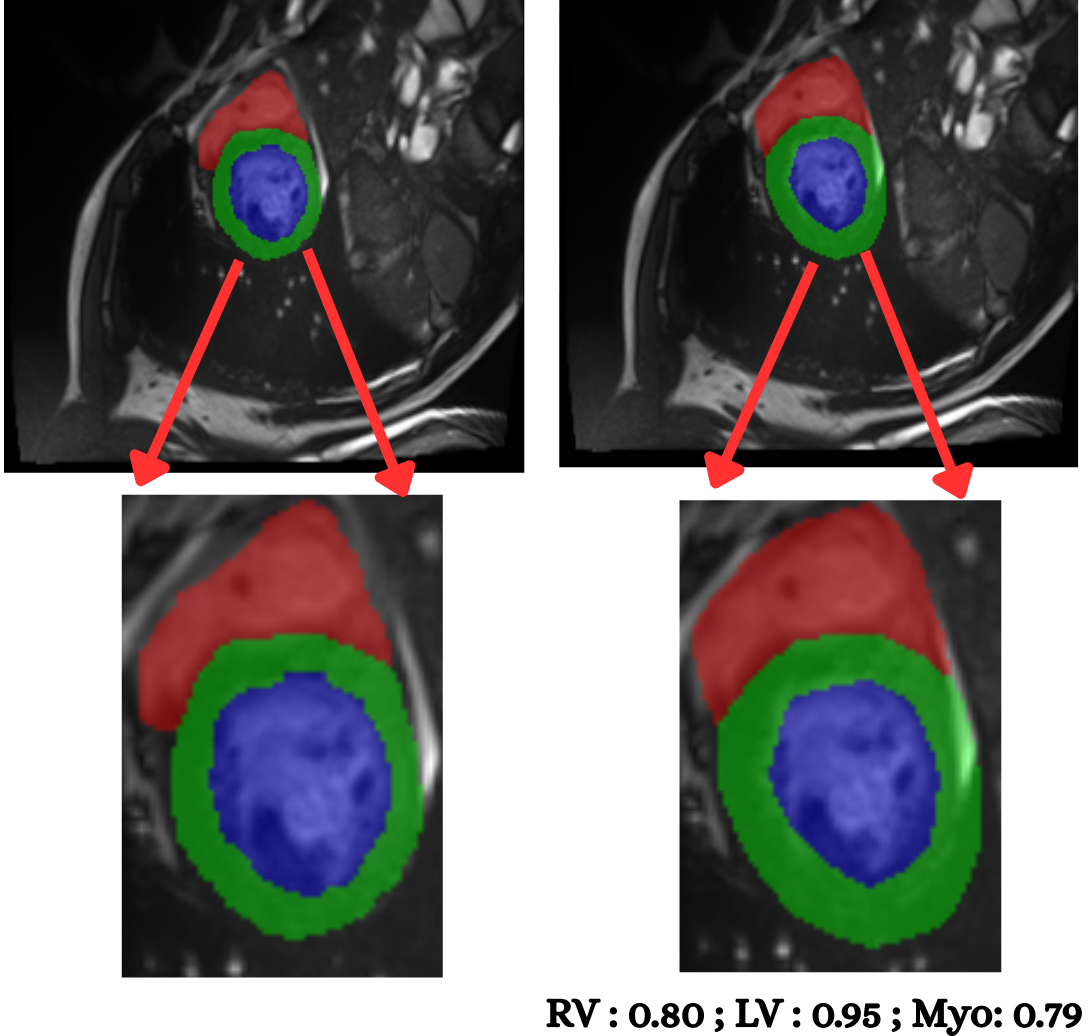

5.2 M&Ms Cine-MRI Generalization

Figure 8 illustrates segmentation outputs on the M&Ms (Multi-Centre, Multi-Vendor) cine-MRI dataset, which exhibits both contrast variation and vendor–specific acquisition differences compared to ACDC. The model retains consistent ventricular geometry, recovering LV and Myocardium structure without retraining, mirroring the zero-shot Dice performance of 74.8% (Table 11). Boundary thickness remains physiologically accurate, with only minor degradation in the right ventricle, an expected behaviour under cross-domain shifts and also reflected quantitatively in the ablation-driven robustness improvements from normalization and loss design. These results demonstrate that PULSE does not overfit to a single scanner distribution but instead transfers cardiac structure priors across unseen clinical environments.